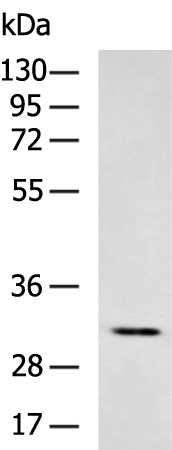

分类: 科研抗体货号: P13257别名: A4; MAM; DMDA; SCG3; 35DAG; DAGA4; DMDA1; LGMD2C; LGMDR5; SCARMD2; gamma-SG应用: WB,IHC反应种属: Human, Mouse